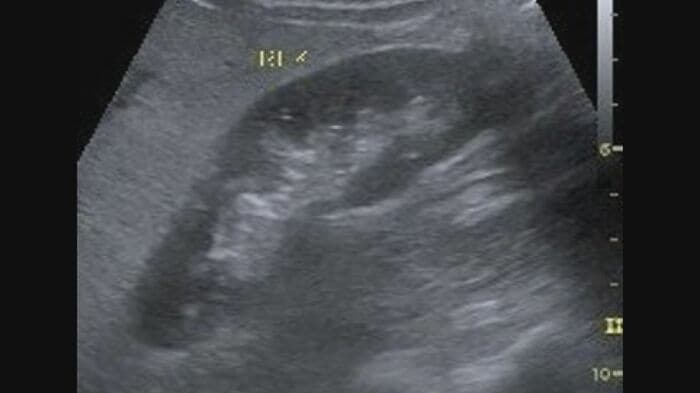

肝臓は、糖質や脂質を中性脂肪に変える役割を担い、この中性脂肪はある程度は血中に流されるものの、代謝が間に合わず過剰となったものは肝臓に蓄積する。これが脂肪肝だ。